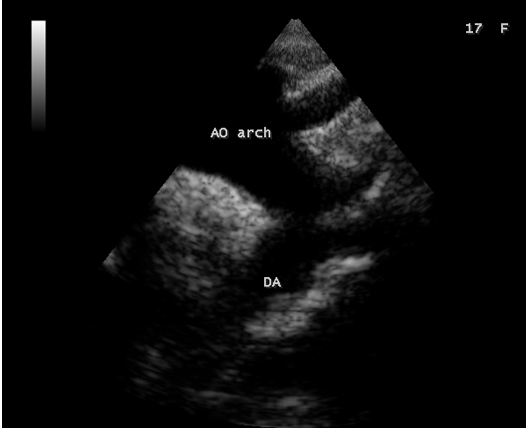

Figure 14: Suprasternal view showing the prominent aortic arch in a 17-year old female in acute severe aortic regurgitation.

Since the patient had a bicuspid aortic valve as shown in Figure 9 and a history of rheumatic fever during childhood, rheumatic inflammation occurred on the aortic valve and harboured the infective vegetation through the vascular access during the treatment of febrile episodes. Patients with infective endocarditis are at risk of developing acute aortic regurgitation and the ECG can appear normal as in Figure 1 and the chest X-ray usually shows pulmonary edema with normal heart size. A dilated left ventricular cavity with a normal left atrium as in Figure 12 indicates that the volume overload on the left ventricle resulted a compensatory mechanism to maintain an adequate forward stroke volume by accomodating a large regurgitant fraction without an increase in end-diastolic pressure. The heart rate appeared normal (87 bpm) as the result of this compensation. Even though the aortic regurgitation is acute as in Figure 10 which showed a steep deceleration slope with a narrow width of regurgitant jet due to endocarditic lesion of aortic valve (endocarditic regurgitation). It is compensated in this patient and showed a lesser degree of decompensation as moderate LV dysfunction with an ejection fraction of 42% as in Figure 13, necessitating elective aortic valve replacement along with removal of vegetations with a mechanical prosthetic valve. Anticoagulation with warfarin to maintain the INR (international normailised ratio) between 2 to 3 is indicated after the clearance of active stage of endocarditis with antibiotic therapy and surgery.